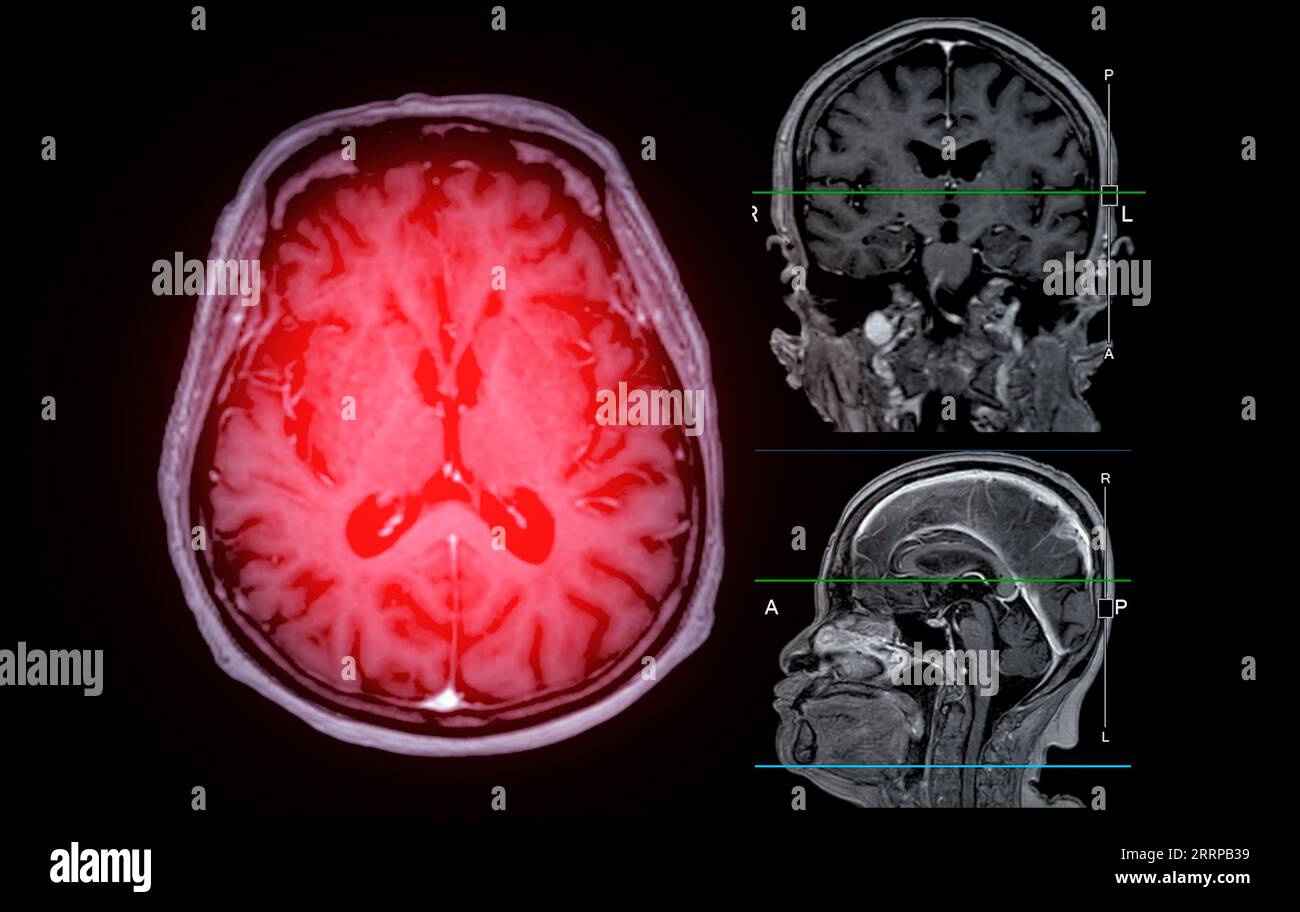

What Can Mri Scans Detect In The Brain. A variant called mr angiography. an mri of the brain can be used to evaluate many symptoms which may be caused by abnormalities in the central nervous system. mra can also be used to detect aneurysms in the brain and vascular malformations — abnormalities of blood vessels in the brain,. doctors use mri scans to diagnose and monitor head injuries and to check for abnormalities in the head or brain. mri can detect abnormalities that might be obscured by bone with other imaging methods. With the mri results in hand,. a head mri is a useful tool for detecting a number of brain conditions, including: using an mri scan, doctors can identify any bleeding or swelling in the brain and determine the extent of any damage. Aneurysms, or bulging in the blood vessels of the brain. mri is used to analyze the anatomy of the brain and to identify some pathological conditions such as cerebrovascular incidents, demyelinating.

A variant called mr angiography. Aneurysms, or bulging in the blood vessels of the brain. With the mri results in hand,. an mri of the brain can be used to evaluate many symptoms which may be caused by abnormalities in the central nervous system. mri can detect abnormalities that might be obscured by bone with other imaging methods. doctors use mri scans to diagnose and monitor head injuries and to check for abnormalities in the head or brain. mri is used to analyze the anatomy of the brain and to identify some pathological conditions such as cerebrovascular incidents, demyelinating. mra can also be used to detect aneurysms in the brain and vascular malformations — abnormalities of blood vessels in the brain,. using an mri scan, doctors can identify any bleeding or swelling in the brain and determine the extent of any damage. a head mri is a useful tool for detecting a number of brain conditions, including:

What Can Mri Scans Detect In The Brain mri is used to analyze the anatomy of the brain and to identify some pathological conditions such as cerebrovascular incidents, demyelinating. mra can also be used to detect aneurysms in the brain and vascular malformations — abnormalities of blood vessels in the brain,. mri is used to analyze the anatomy of the brain and to identify some pathological conditions such as cerebrovascular incidents, demyelinating. A variant called mr angiography. an mri of the brain can be used to evaluate many symptoms which may be caused by abnormalities in the central nervous system. using an mri scan, doctors can identify any bleeding or swelling in the brain and determine the extent of any damage. a head mri is a useful tool for detecting a number of brain conditions, including: With the mri results in hand,. doctors use mri scans to diagnose and monitor head injuries and to check for abnormalities in the head or brain. mri can detect abnormalities that might be obscured by bone with other imaging methods. Aneurysms, or bulging in the blood vessels of the brain.